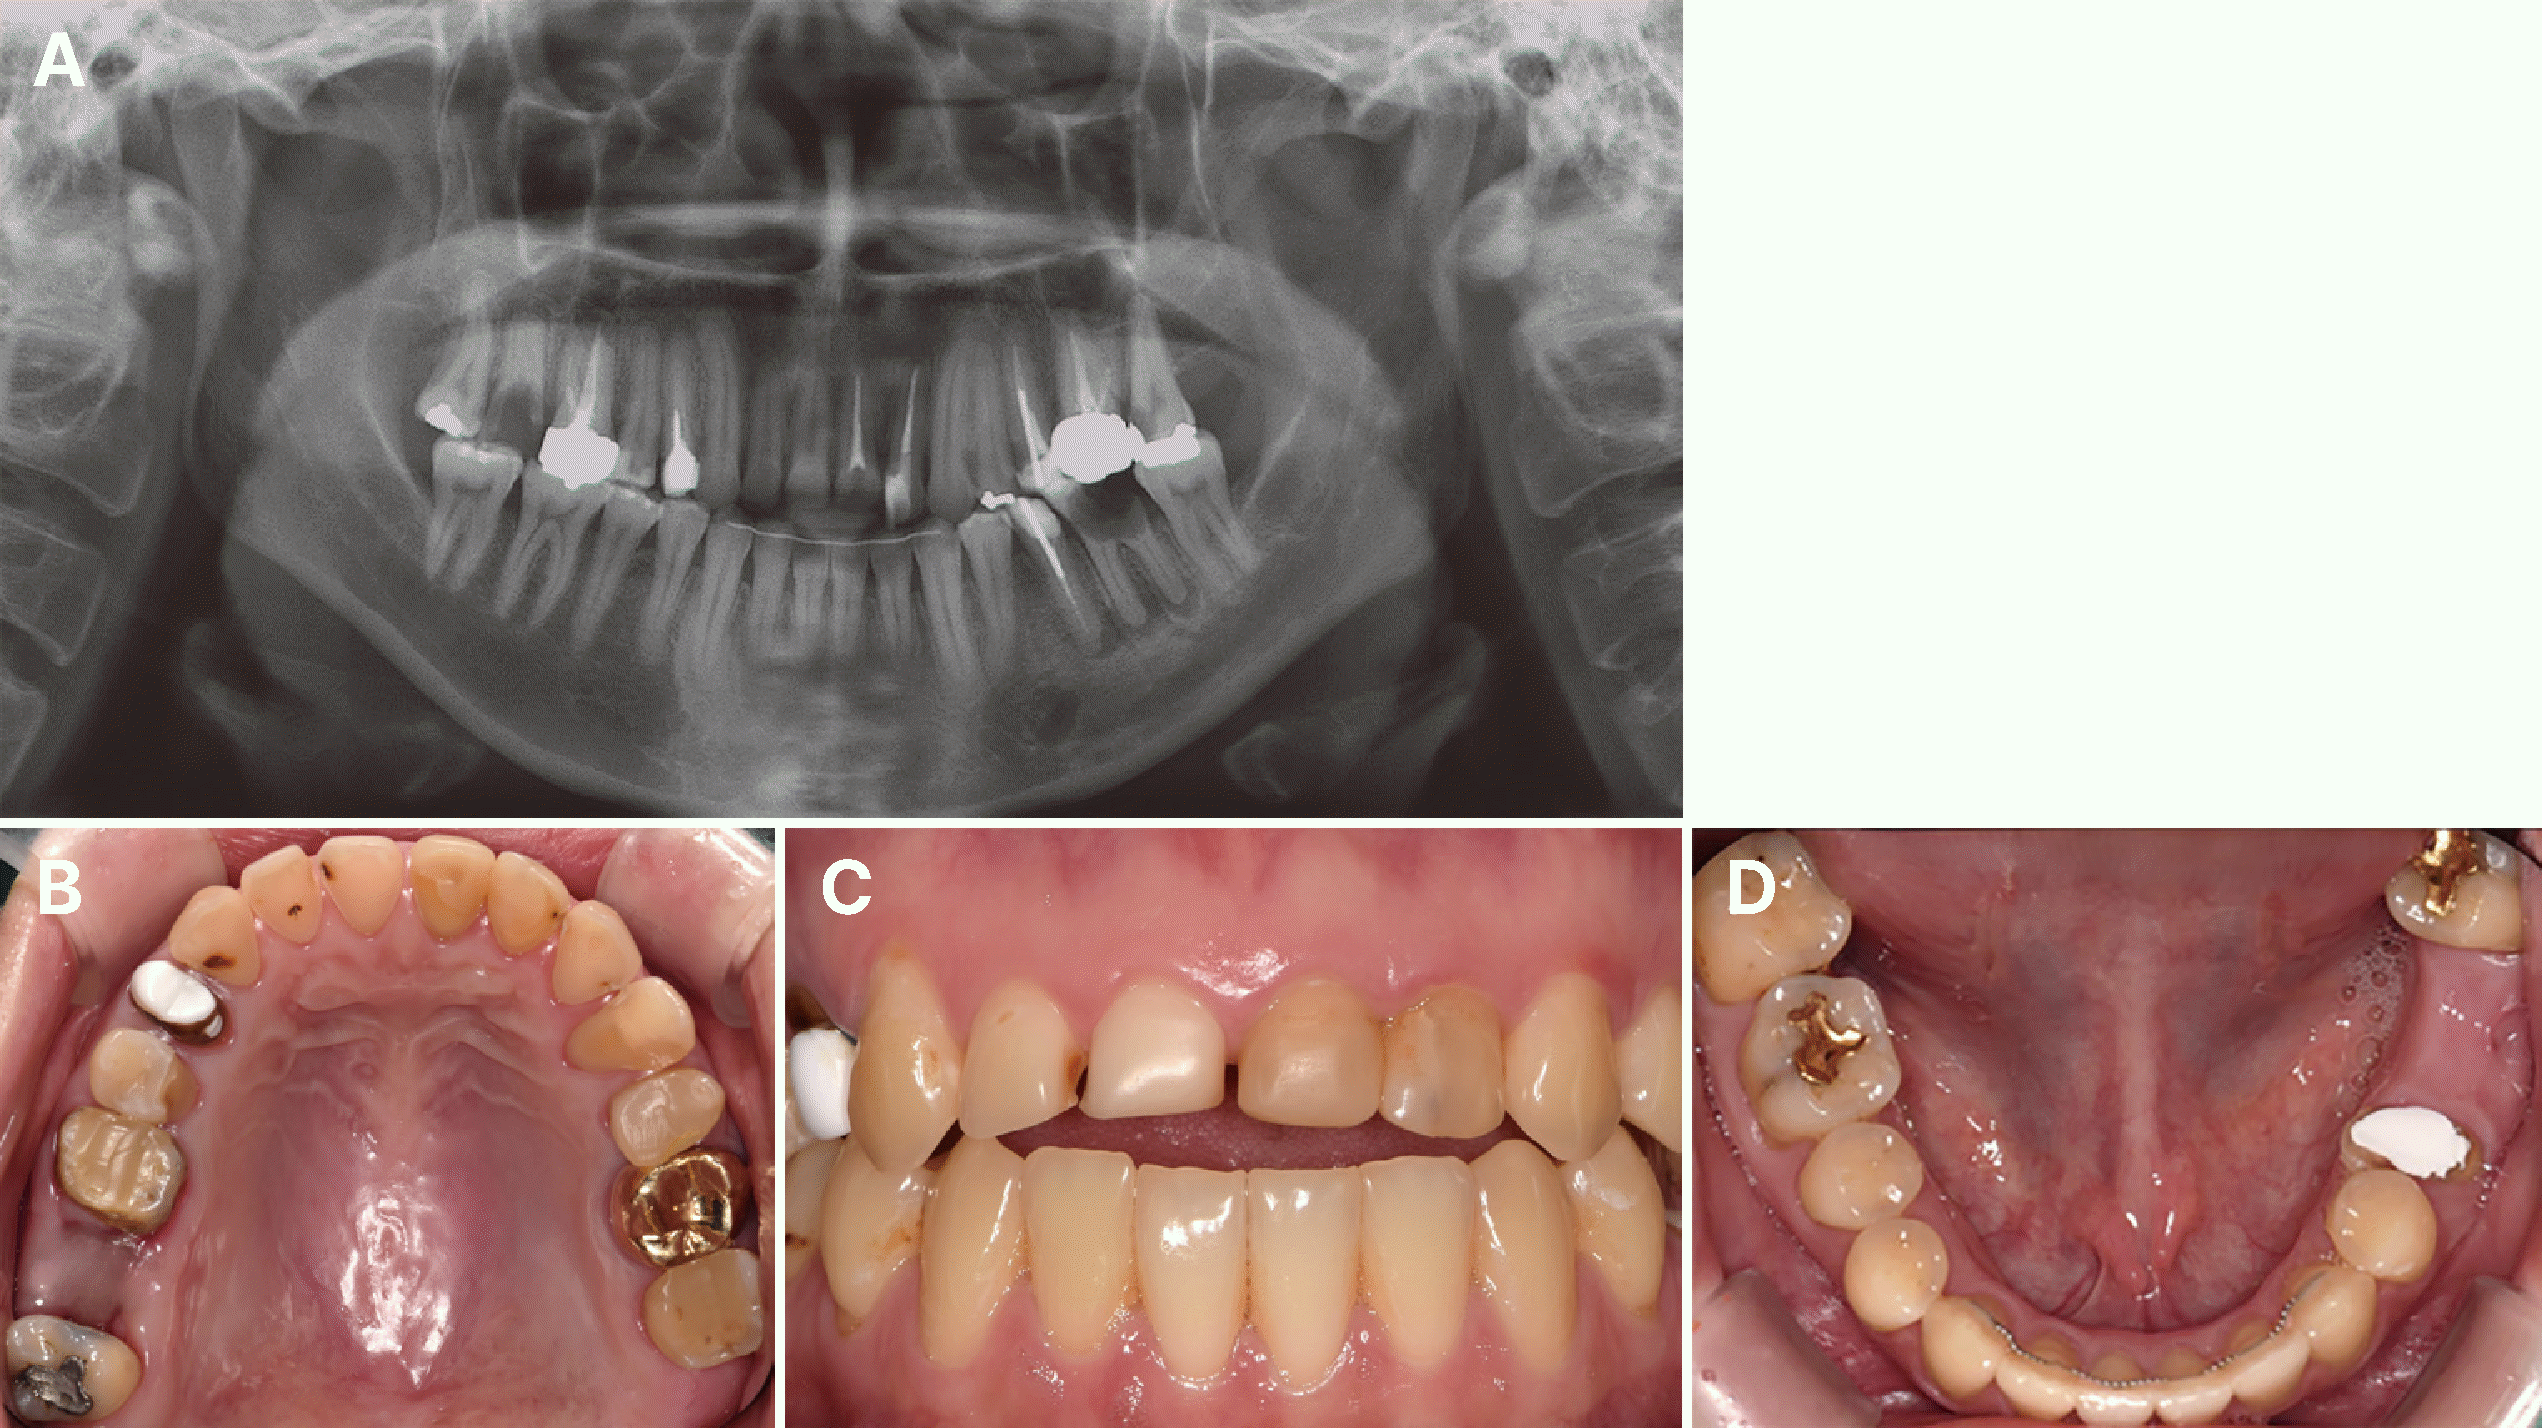

상기 환자는 20대 여성으로, 저작 불편을 주소로 내원하였다. 의과적 병력으로 신경성 폭식증을 가지고 있었으며 구외 평가 시, 상악 전치부의 심한 부식으로 인해 미소 시 하순의 상연과 반대되는 형태의 오목한 미소선이 관찰되었다. 초진 방사선사진 검사 상 상악 전치부를 포함한 다수의 치아에 우식이 관찰되었고, 이 중 상악 우측 제2구치와 하악 좌측 제1대구치는 광범위한 우식을 보였다. 구치부에는 치근단 병소가 존재하였으며, 광범위한 우식으로 인해 우측 상악 제2구치와 좌측 하악 제1대구치는 발거를 결정하였다. 구내 검사 시 상악 치열의 전반적인 부식이 존재했는데 그 중 전치부 구개측 부식이 특징적으로 확인되었고, 비심미적인 코어가 관찰되며 상악 대구치는 치관 수복물이 제거된 상태였다(Fig. 1).

Fig. 1

Initial examination. (A) Panoramic x-ray, (B) Maxillary occlusal view, (C) Frontal view, (D) Mandibular occlusal view.